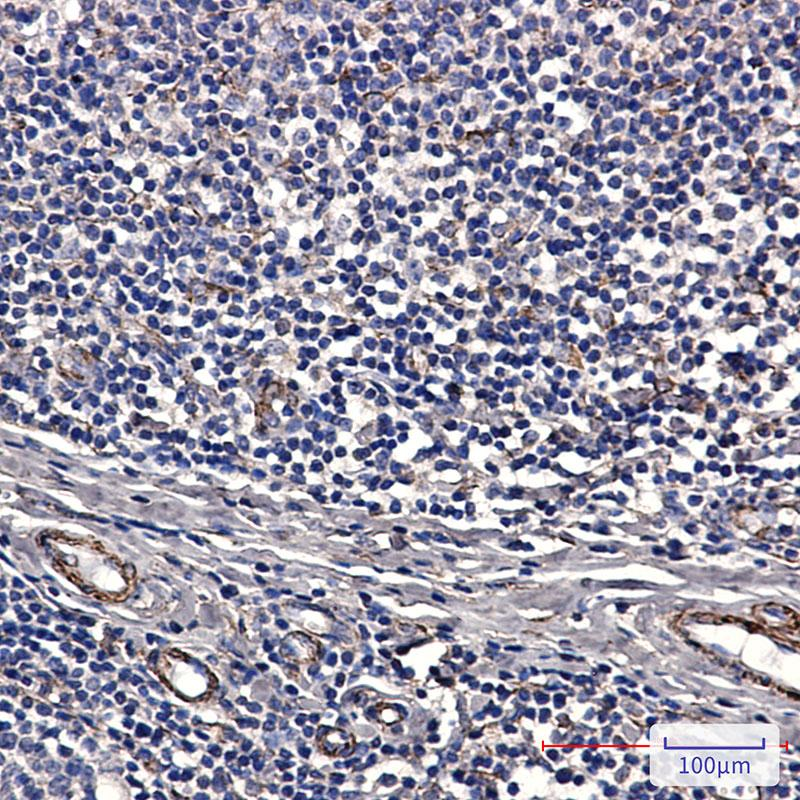

2026石蜡切片免疫组化抗体

病理诊断是疾病诊疗体系的基石,而石蜡切片免疫组织化学技术则为这一基石注入了精准定位的内核。